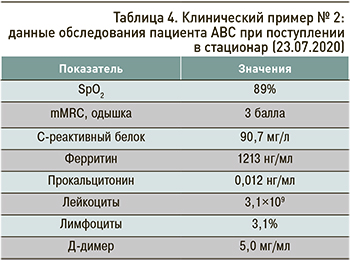

Данные обследования пациента при поступлении отражены в таблице 4.